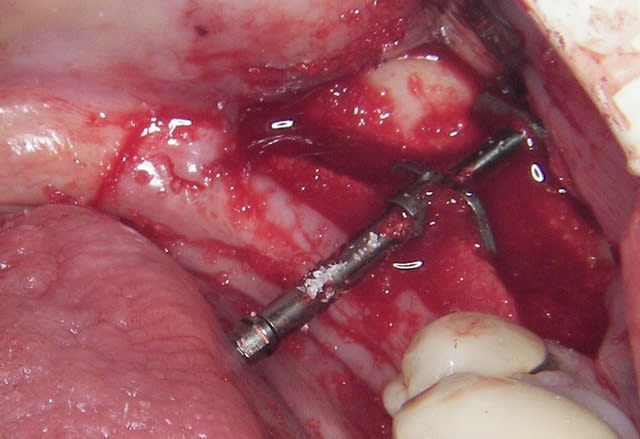

L’incision est décalée par rapport à la crête, en vestibulaire, car je ne veux pas décoller le périoste sur la partie osseuse qui est mobilisée.

Je pense que ça permet de "nourrir" le "greffon" et surtout si la table interne venait à se rompre le "greffon" ne serait que semi-mobile.

J’ai donc fait une expansion verticale et latérale puisque je n’ai pas coupé la corticale linguale, du moins dans sa partie postérieure, et j’espère gagner sur les deux tableaux, mais il était risqué de mettre en plus les implants.

Il y a deux incisions séparées de 1,5 à 2mm, initiées au disque (double comme sur les motos) et finies au piézo

Il est illusoire de croire que l'os mandibulaire se laisse "pénétrer" simplement.

Et surtout il faut pouvoir retirer le distracteur ensuite.